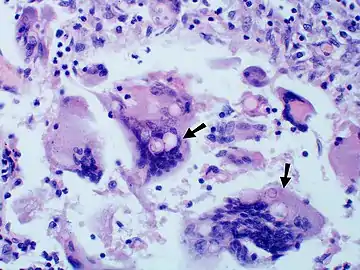

Granuloma with early suppuration. Fungal organisms difficult to recognize at this low magnification.

Large yeast-like fungi seen within giant cells at arrows.

Large yeast-like fungi seen within giant cells at arrows. Budding yeasts in cytoplasm of giant cells at arrows. Broad-based budding and double contoured cell wall seen in the giant cell in the center is characteristic of Blastomyces dermatitidis.